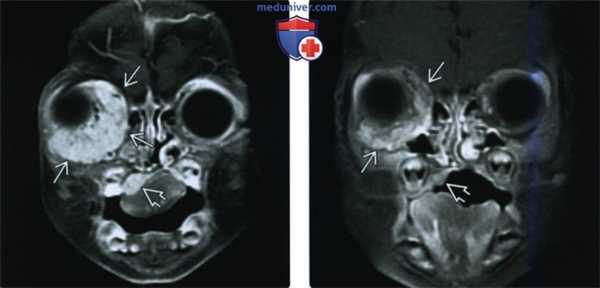

(Слева) При корональной МРТ Т1ВИ С+ FS у двухмесячного ребенка визуализируется крупная МГ, интенсивно накапливающая контраст, находящаяся как внутри, так и снаружи мышечной воронки глазницы; видно также другое объемное образование в области неба справа.

(Справа) При корональной МРТТ1ВИ С+ FS у этого же пациента шесть месяцев спустя после лечения пропранололом с целью предотвращения осложнений со стороны глазницы определяется существенный регресс объемных образований в глазнице и небе.